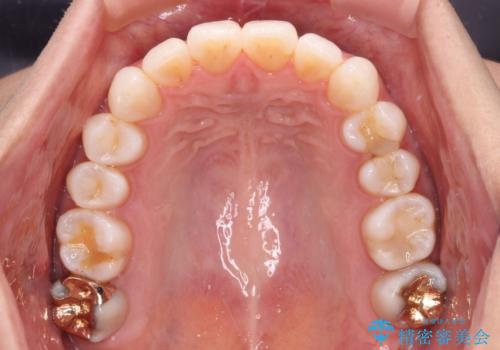

- 少しだけ前に飛び出ている前歯を気にして来院された患者様です。

上顎歯列全体を後方に移動させる必要があり、インビザライン単体での治療は困難と判断し、補助装置により左右側方歯列を移動させた後にインビザラインを用いることとしました。

インビザライン単独でも上顎歯列全体を後方移動することで臼歯の咬み合わせを改善できる場合もあります。しかしながら、矯正治療は当初設定したゴールに到達する必要があり、今回のような場合ではインビザライン単独では達成の可能性が低くなるので、補助装置を使用して、より確実に治療を行うこととしています。